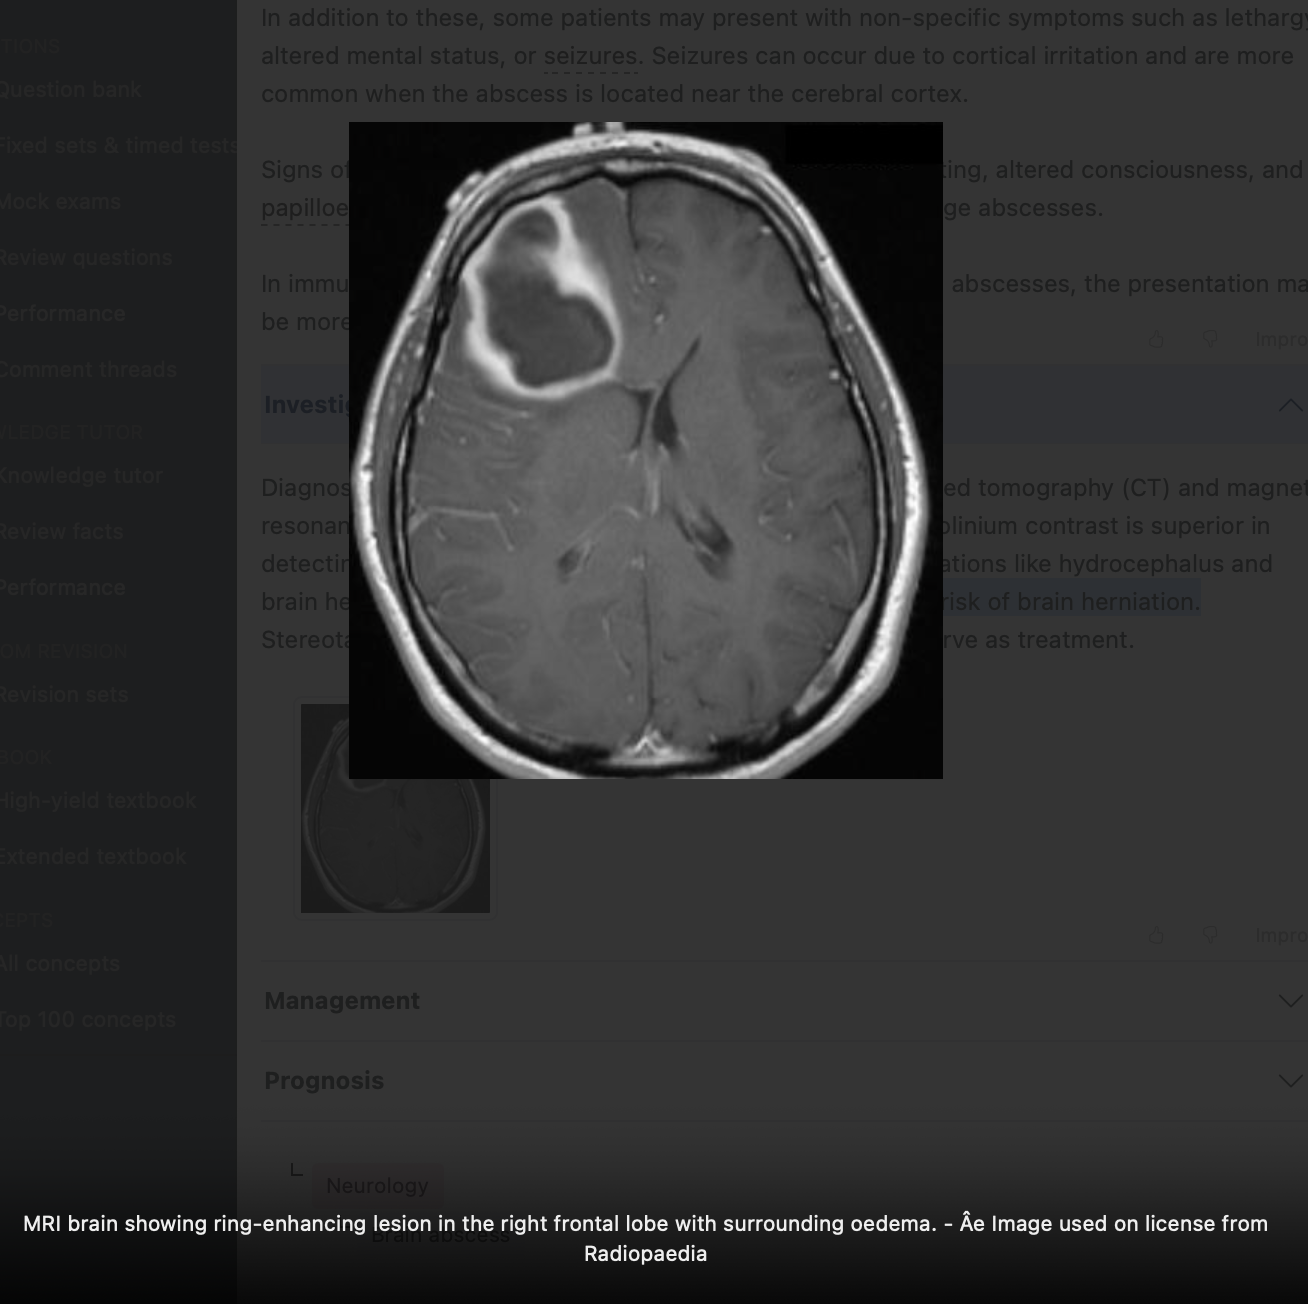

MRI with gadolinium contrast is superior in detecting early cerebritis

CT is useful for detecting complications like hydrocephalus and brain herniation.

Stereotactic needle aspiration can both aid diagnosis and serve as treatment.

NB: Lumbar puncture is contraindicated due to risk of brain herniation.